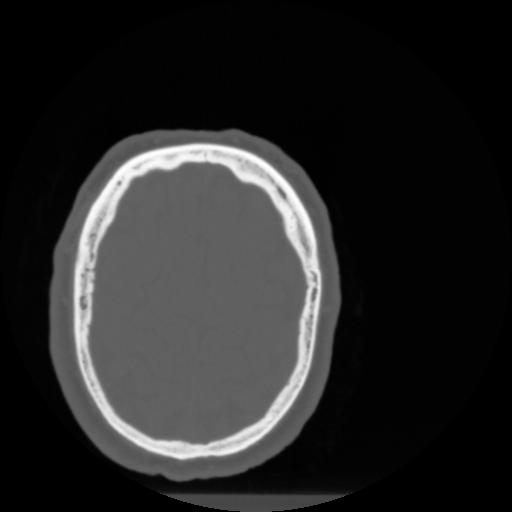

4 CEREBRO,,Vol,0.5,CEREBRO,,